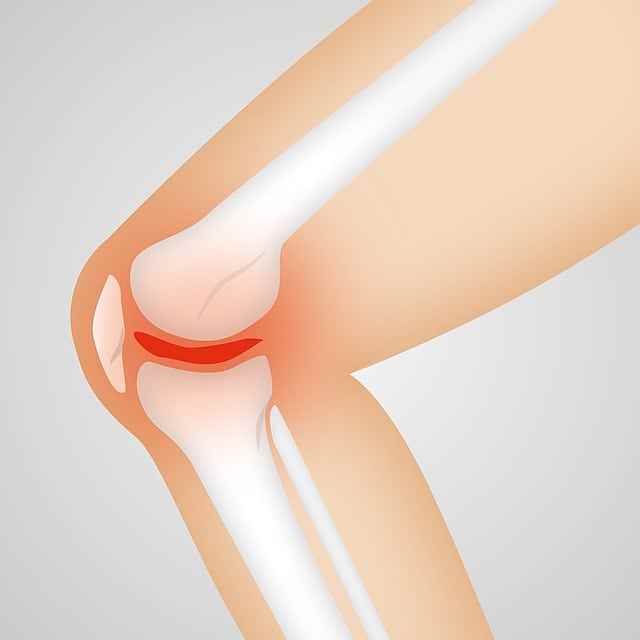

6. 외상이나 골절

골다공증의 특징적인 증상 중 하나는 외상이나 힘이 거의 없는 상태에서 골절의 위험이 증가한다는 것입니다. 허리를 굽히거나 기침을 하거나 심지어 가벼운 돌기가 있는 경우에도 골절이 발생할 수 있는데, 특히 엉덩이, 척추, 손목과 같은 체중이 많이 나가는 뼈에 골절이 발생할 수 있습니다. 큰 부상 없이 골절을 경험했다면, 향후 골절과 합병증을 예방하기 위해 의사와 함께 뼈 건강에 대한 근본적인 관심사를 조사하는 것이 필수적입니다.